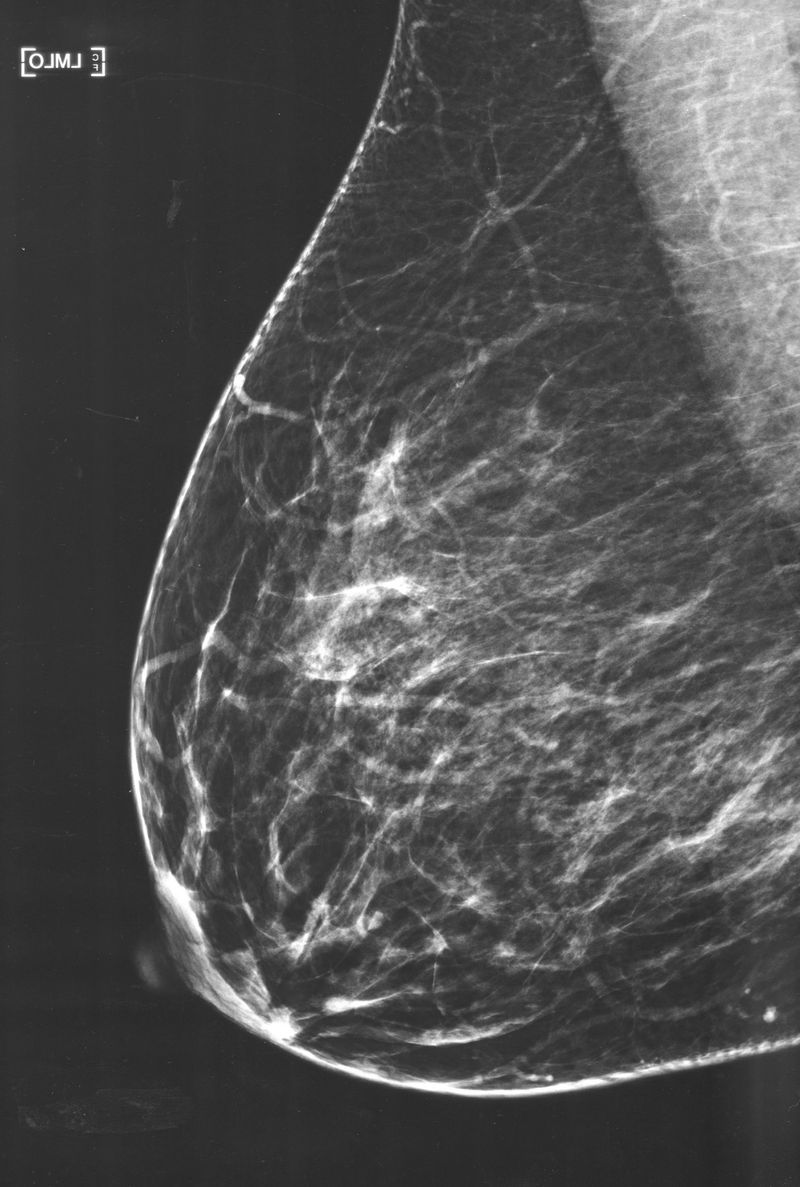

"Mleko" is a visual research project born from my fascination with human milk and its intricate nature. Following the birth of my first child in 2021, I was captivated by this biological substance uniquely tailored to nourish my son.

"Mleko" (2021-2024) is a visual research project born from my fascination with human milk and its intricate nature. Following the birth of my first child in 2021, I was captivated by this biological substance uniquely tailored to nourish my son. This curiosity propelled me to delve deeper into the multifaceted dimensions of human milk and the experience of breastfeeding.

In “Mothers; An Essay on Love and Cruelty”, Jacqueline Rose writes that; “The supreme symbol of mother love is, of course, the breast, which reappears in modern discussions of motherhood”, which makes the subject of breastfeeding central and opinionated. Milk is breaching a gap between milk giver and child, between an animal and human, between self and other, between myth and world.

My project is structured into three parts:

My Milk: This segment offers an intimate exploration of my journey with breastfeeding, capturing the physical and emotional nuances of this experience.

Their Milk: Here, I broaden the perspective by documenting the experiences of other breastfeeding women, highlighting the collective narratives and shared challenges.

Our Milk: This final part examines the societal and cultural contexts surrounding human milk, incorporating insights from lactation experts, milk banks, and milk donors.

Through a blend of photography, text, video, and audio interviews, "Mleko" aims to demystify human milk, encouraging open dialogue and reducing the stigma associated with breastfeeding in both public and private spheres.